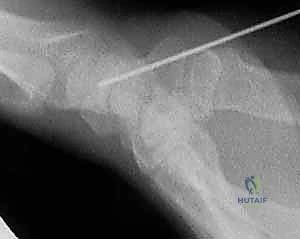

TECH FIG 1 • The scaphoid ring sign indicates the central axis of the scaphoid, which is critical for accurate insertion of the cannulated compression screw. A,B. The wrist is positioned in flexion and pronation until the scaphoid appears as a ring (

arrow

) on fluoroscopic imaging. A 0.045-inch guidewire is inserted through the center of the ring.